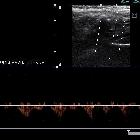

Subclavian

vein aneurysm - Case presentation and discussion. Gray scale and Color Doppler exploration demonstrates the aneurysm and an echogenic image attached to a wall in its interior, compatible with mural thrombus.

vein aneurysm - Case presentation and discussion. Gray scale and Color Doppler exploration, orthogonal to Fig. 3a, demonstrates the aneurysm and an echogenic image attached to a wall in its interior, compatible with mural thrombus.

vein aneurysm - Case presentation and discussion. Gray scale and Color Doppler exploration, showing evidence of the patency of the subclavian vein adjacent to the aneurysm.